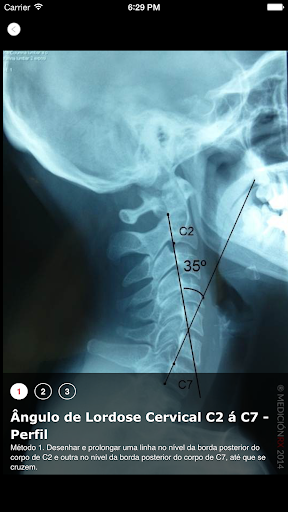

é o app no qual você encontrará a descrição e o traçado das técnicas de medição radiológicas em ortopedia e traumatologia. 120 imagens radiográficas de alta qualidade. Dirigida a fisioterapeutas especialistas nas áreas de terapia manual (RPG, osteopatia, etc.), etc. Você poderá realizar sua busca, digitando "regiões", "patologias" ou "medições". Você também poderá realizar sua busca inserindo a palavra-chave na lupa de busca. Não é o objetivo deste app, substituir avaliação clínica que fazemos aos nossos pacientes. Este app tem como objetivo explorar os métodos de medição em estudos radiológicos complementários, e demonstrar e quantificar as alteracoes radiológicas obtidas após os tratamentos kinésicos. Esta aplicação está disponível em Português, Espanhol e Inglês.